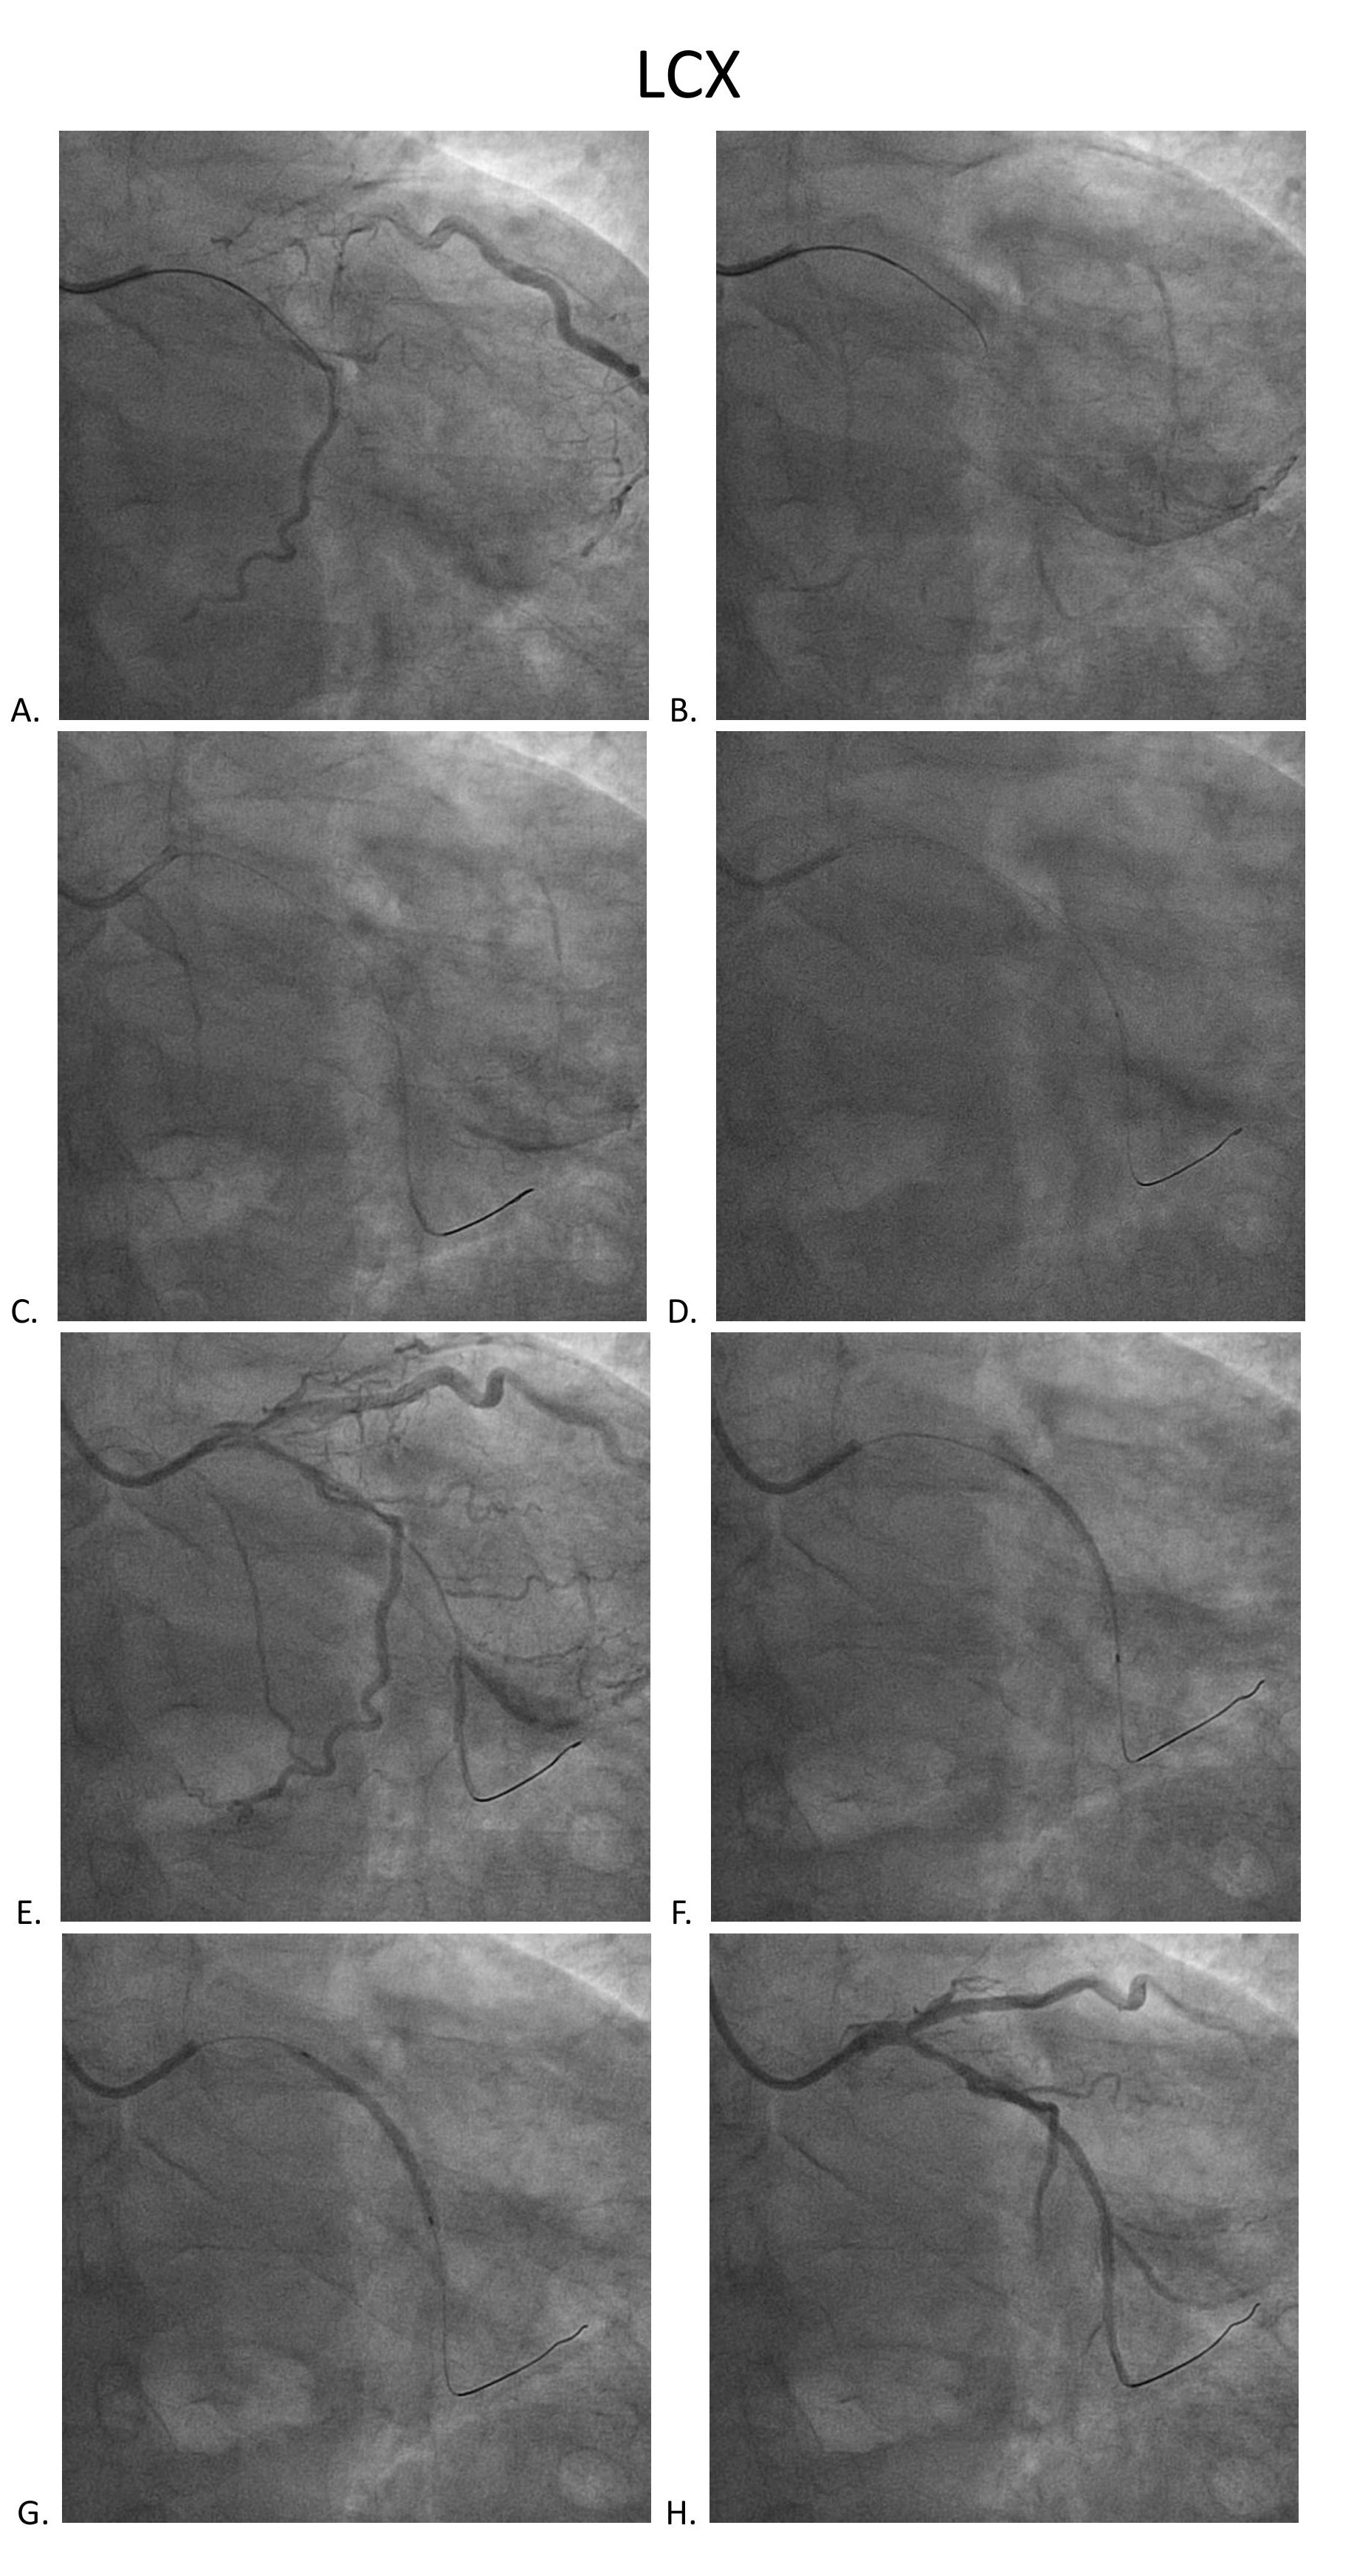

Coronary angiography disclosed orifice total occlusion with TIMI grade 0 antegrade flow at LAD, middle total occlusion at LCX, and RCA proximal total occlusion with auto-collateral to RCA distal.

SCR guiding cath was used to engage RCA. Runthrough wire, Conquest pro, and Conquest 860 wire were used to get cross the CTO lesion. Resolute 2.75x38mm stent was inflated after predilatation with different size BC. XB 3.0x6fr guiding cath was used to engage LCX. Sion blue, Conquest pro, and Fielder XT-A wire were used to get cross the LCX lesion. Predilatation was done with 1.5x20mm BC, followed by Sierra 2.0x38mm stenting and 2.0x30mm B. Braun DEB.